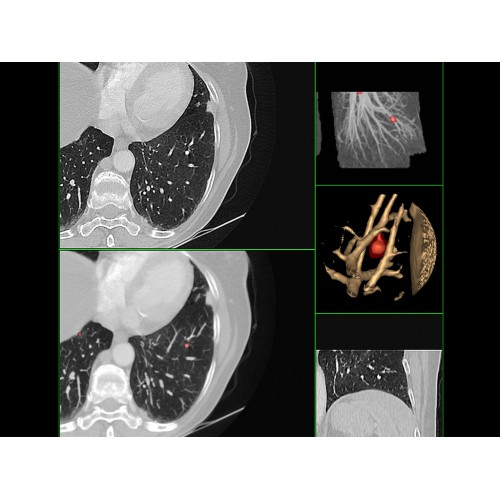

• Широкая область применения: от неврологии до кардиологии и онкологии.

Онкология

• Раннее выявление новообразований и контроль эффективности лечения.

• Планирование лучевой терапии с высокой точностью.